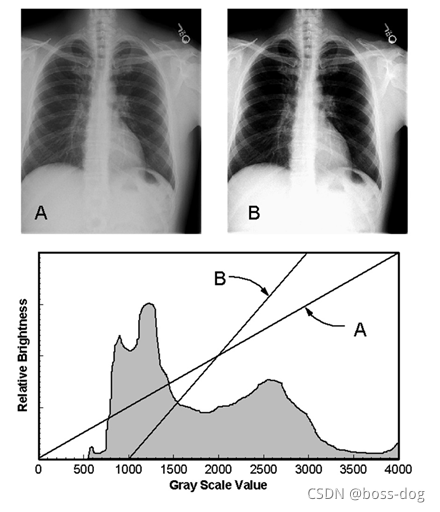

Display contrast(显示器地对比度)

医学图片中希望把最黑的、最亮的、中间的能够完美地显示出来。

上图中如何将灰度转换为显示器上的实际密度:

窗口宽度(Window width,W)

window level(L)

饱和至黑色:L - W/2

饱和至白色:L + W/2

1.检测器信号范围是0-4000计数/像素。

2.PC显示器相对亮度0-2000。

3.图像具有有用区域的信号范围为500-3000计数/像素。

像CT的话,窗口很宽,从负一千到正一千,如果全部显示出来的话,人眼不一定能够把那些细节检测出来看出来,所以针对CT,可以调整图像。